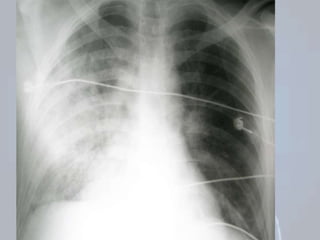

PNEUMOTÓRAX HIPERTENSIVO

 Emergência com risco de morte;

  risco: fratura de costelas, pneumotórax, ventilação +;

Entrada de ar

P

. intratorácica ELEVADA;

Comprometimento ventilatório/ retorno venoso ao coração;

 Troca gasosa  Débito cardíaco

CHOQUE

Desvio do mediastino

AVALIAÇÃO: Apreensão e desconforto; Dor

torácica e dificuldade na respiração; Piora: agitação

crescente e sofrimento respiratório; Casos graves:

cianose e apneia;

 ACHADOS CLÁSSICOS: desvio traqueal,  M.V,

percussão timpânica;

 OUTROS ACHADOS: Turgência venosa jugular,

crepitação da parede torácica e cianose; Taquicardia e

taquipneia ( Pressão) culminando em hipotensão e

choque descompensado.